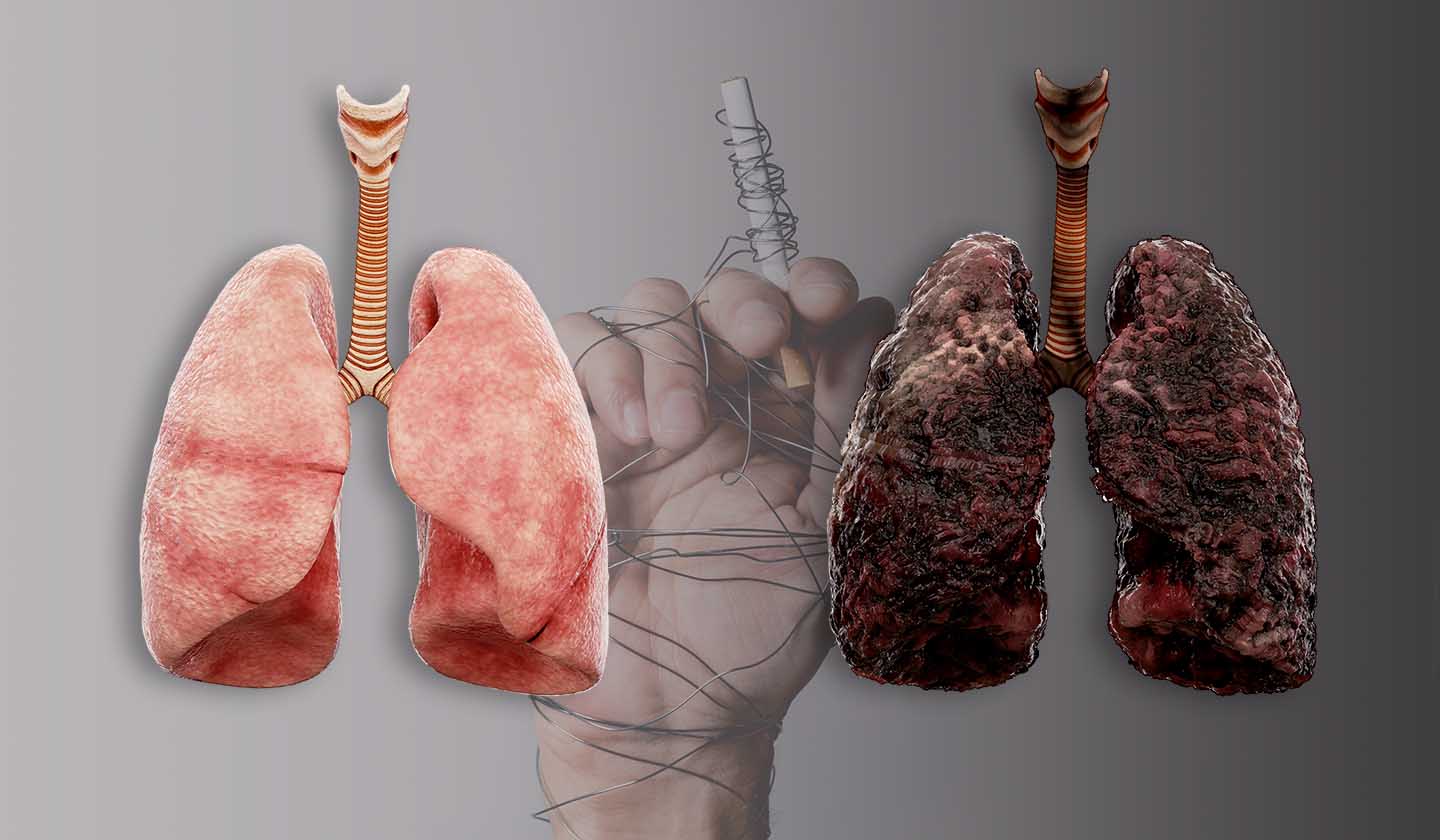

O consumo de tabaco é um grave problema de saúde pública a nível mundial e é a maior causa de morte evitável do mundo. Segundo a Organização Mundial de Saúde (OMS) o tabaco mata atualmente cerca de 7 milhões de pessoas todos os anos e poderá vir a matar mais de 8 milhões por ano, até 2030.

Fumar mata!

A lista de complicações associadas ao tabagismo é longa e inclui:

• Complicações respiratórias – tosse, asma, DPOC, cancro do pulmão (e outros tumores das vias respiratórias) e infeções respiratórias;